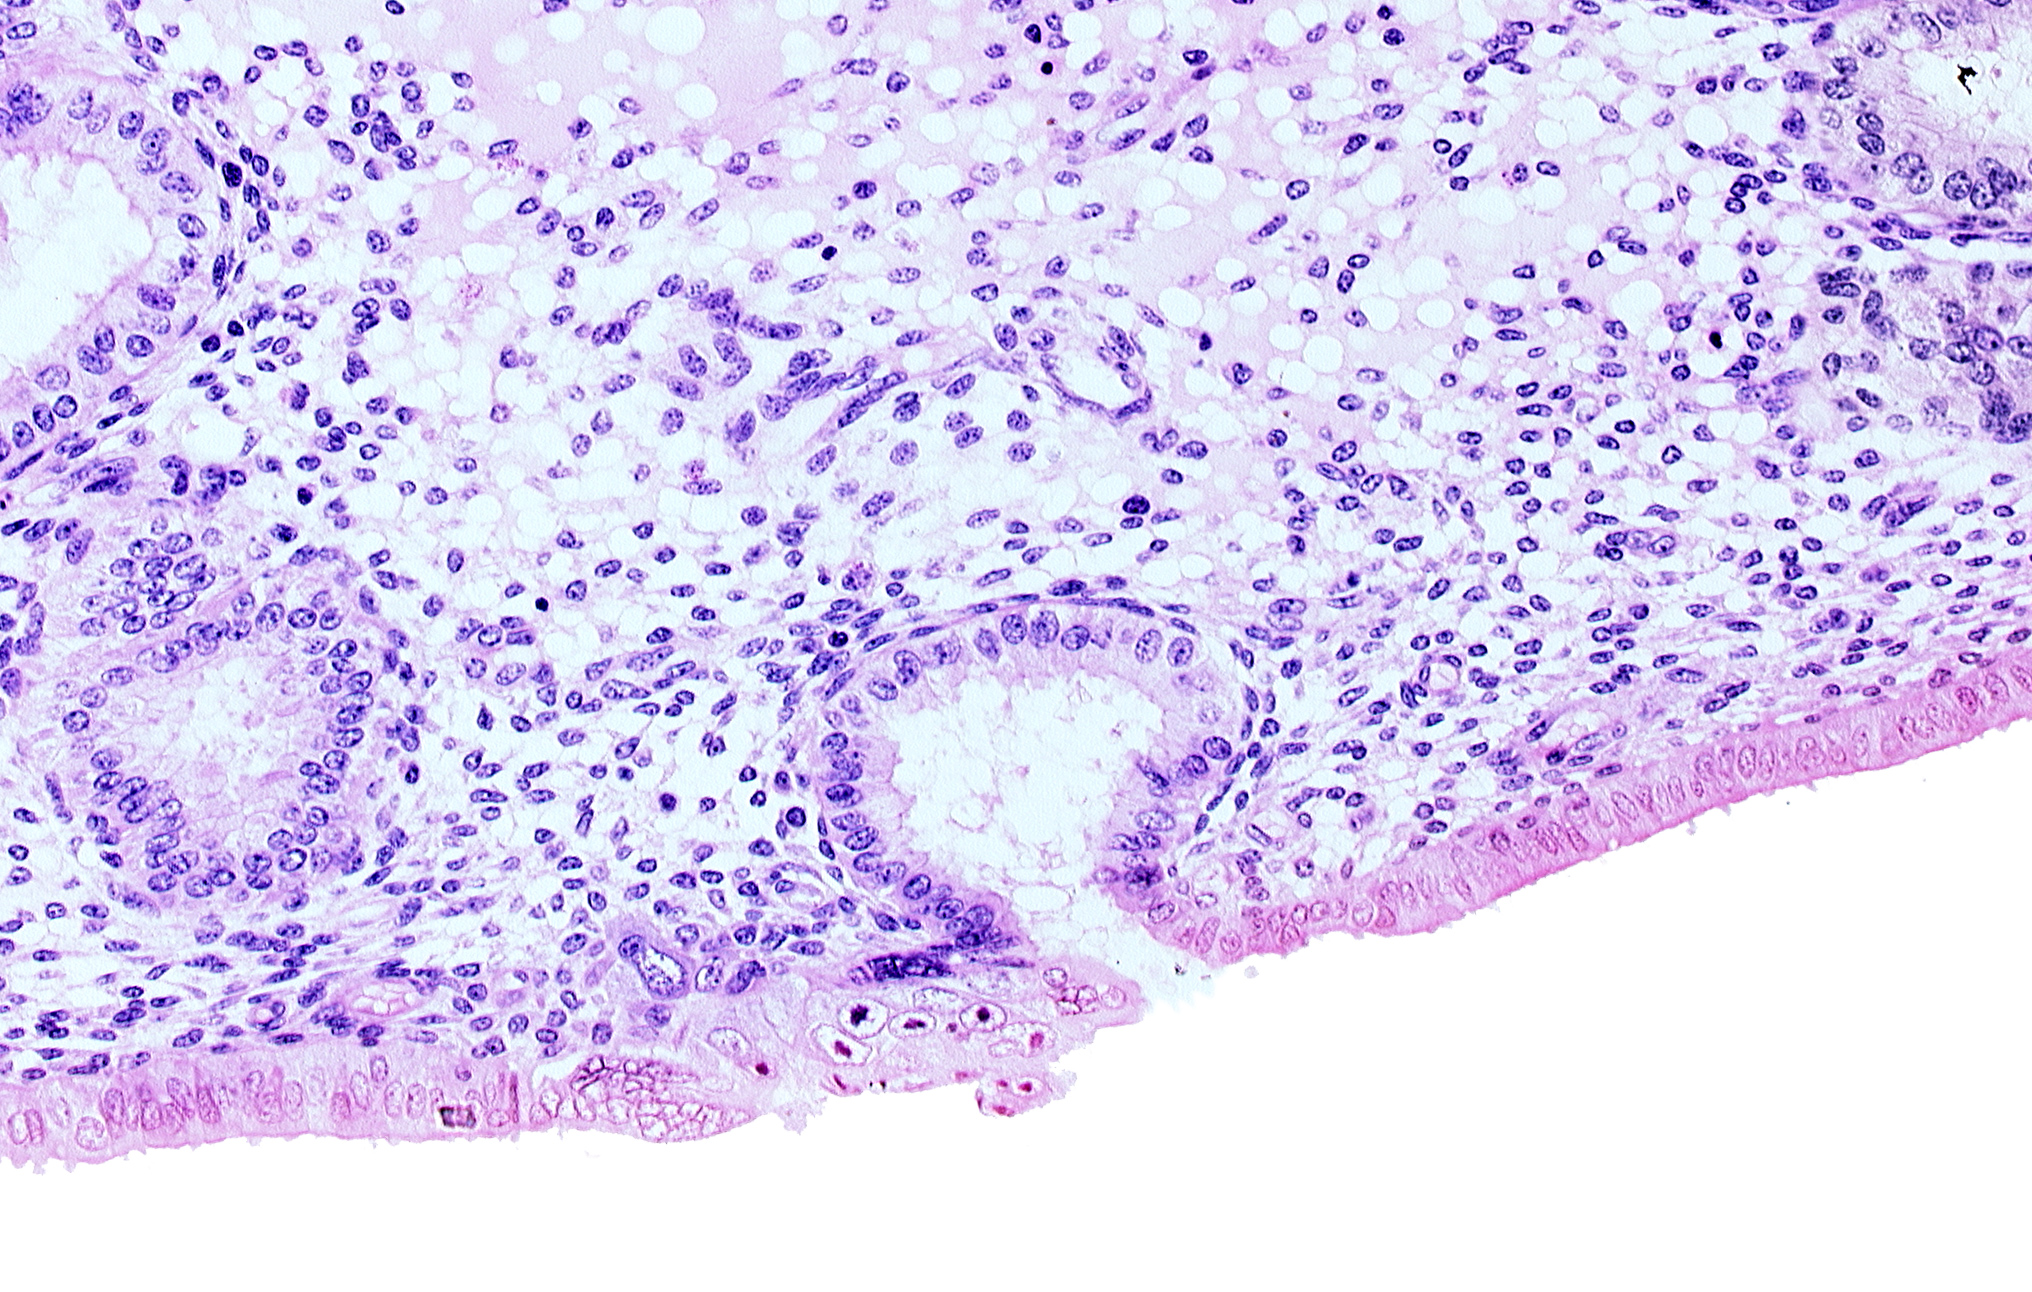

Carnegie Embryo #8020 | Location: 06-05-07

Keywords: endometrial epithelium, lumen of endometrial gland, mouth of endometrial gland, solid syncytiotrophoblast

Source: The Virtual Human Embryo.